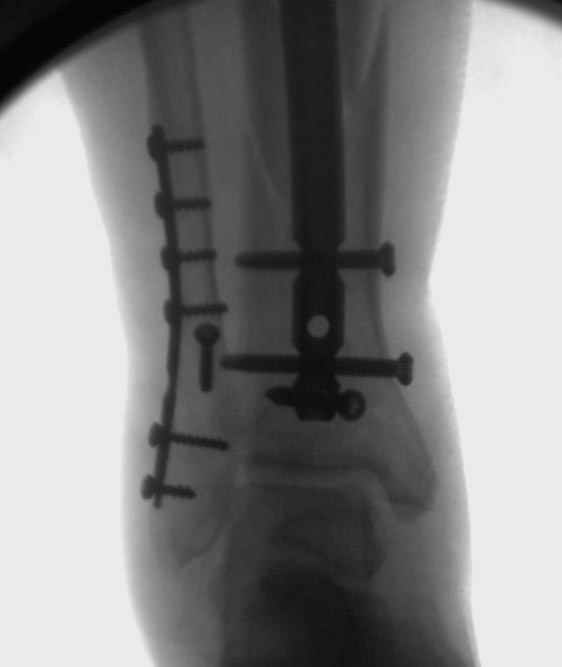

Здесь мы использовали новый Synthes Nail с дополнительными дырками, в проксимальной части 4: по две косых и поперечные (один стандартный а другой динамический), в дистальной части две поперечные, прямая и косая. Вес больного более 120 кг, нагрузку начнем через месяц.

Получилось красиво, поздравляю. Вверху можно было ограничиться одним винтом во фронтальное статическое отверстие, зачем два 45-градусных?

При такий спирали задний край tibia может быть сломан - нет ли этого в данном случае? На всякий случай можно было ввести 1-2 винта 4,5 мм спереди назад мимо гвоздя. Хотя самый дистальный блокирующий винт, возможно, зацепил этот отломок. А какой тут диаметр гвоздя и locking винтов?